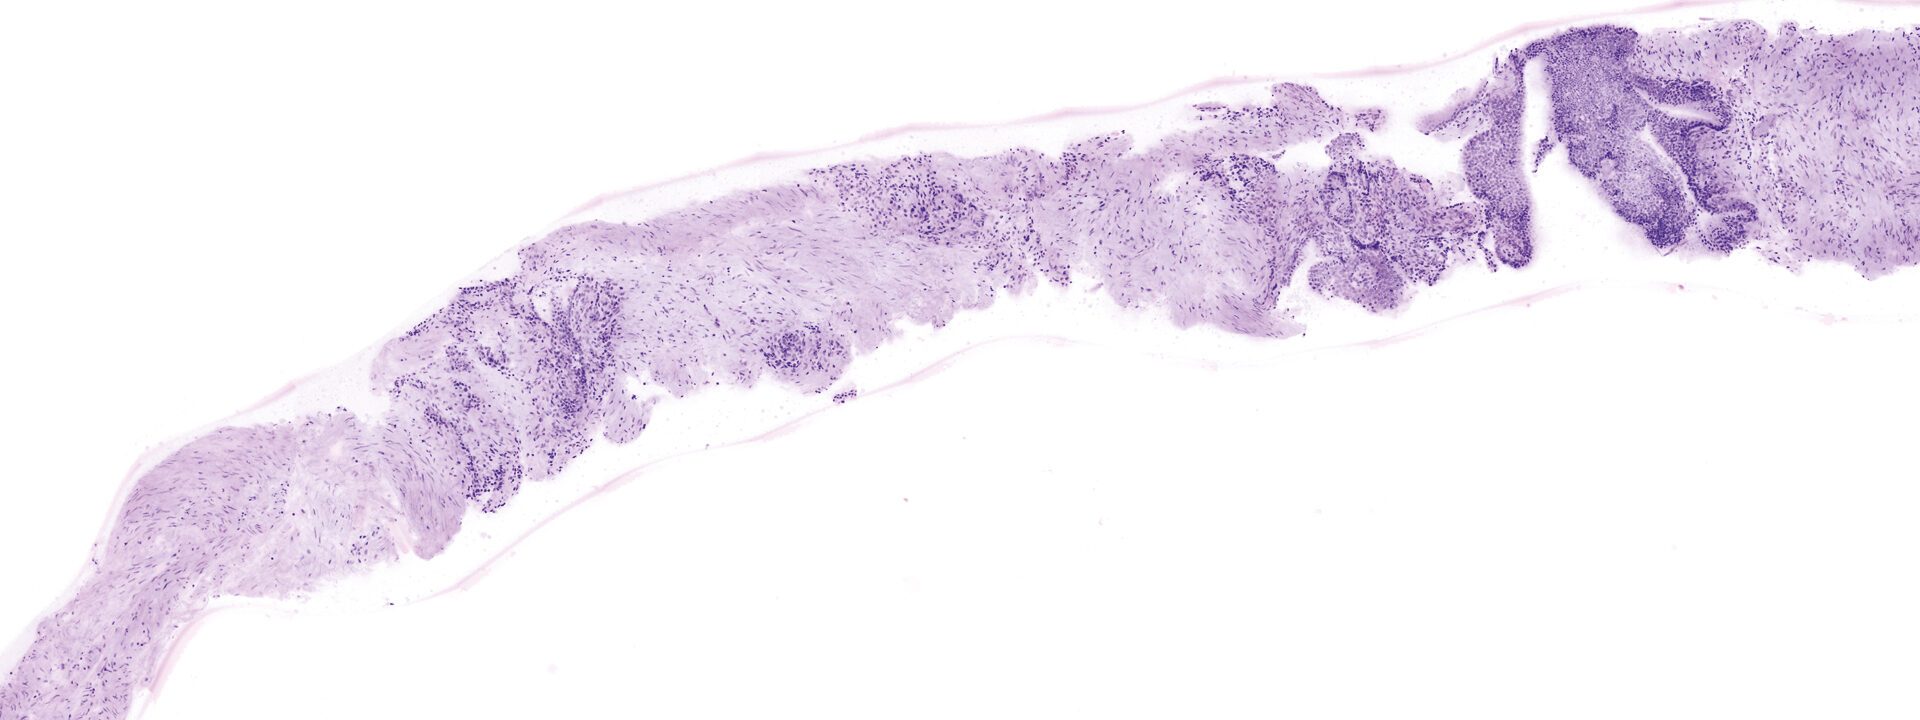

Images courtesy of Dr Javiera Pérez-Anker.

Basal cell carcinoma; imaged with the VivaScope 2500 (left) and after H&E staining (right)

Image courtesy of Dr. Anna Crescenzi, Department of University Hospital Campus Bio-Medico, Rome.